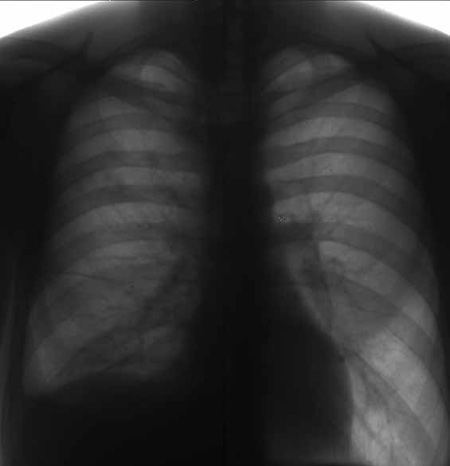

Представляет собой заболевание, поражающее серозную оболочку лёгкого (плевру). Причиной возникновения этого заболевания является инфекционное поражение легких. Туберкулёзный плеврит может возникать как самостоятельное заболевание, а может развиться на фоне других форм туберкулёза.